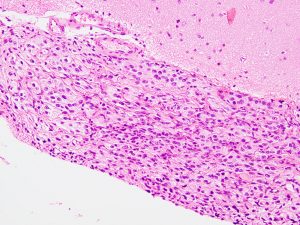

軟膜下伸展とV600Eの変異がある例

てんかん発作が難治化したために全摘出をしてから,3年後に生じた再発のMRI画像です。もともと左下側頭回底部にあって境界明瞭で完全摘出できたと考えていましたが,硬膜に癒着するような小さな脳表面再発が生じました。画像で見える再発像の周囲の軟膜が硬く,周囲表面の脳皮質を含めて,supratotal resectionしました。それ以降,再発はありません。

左は腫瘍の軟膜下の這うような浸潤伸展像です。遺伝子検査では,BRAF V600E遺伝子変異が認められました。